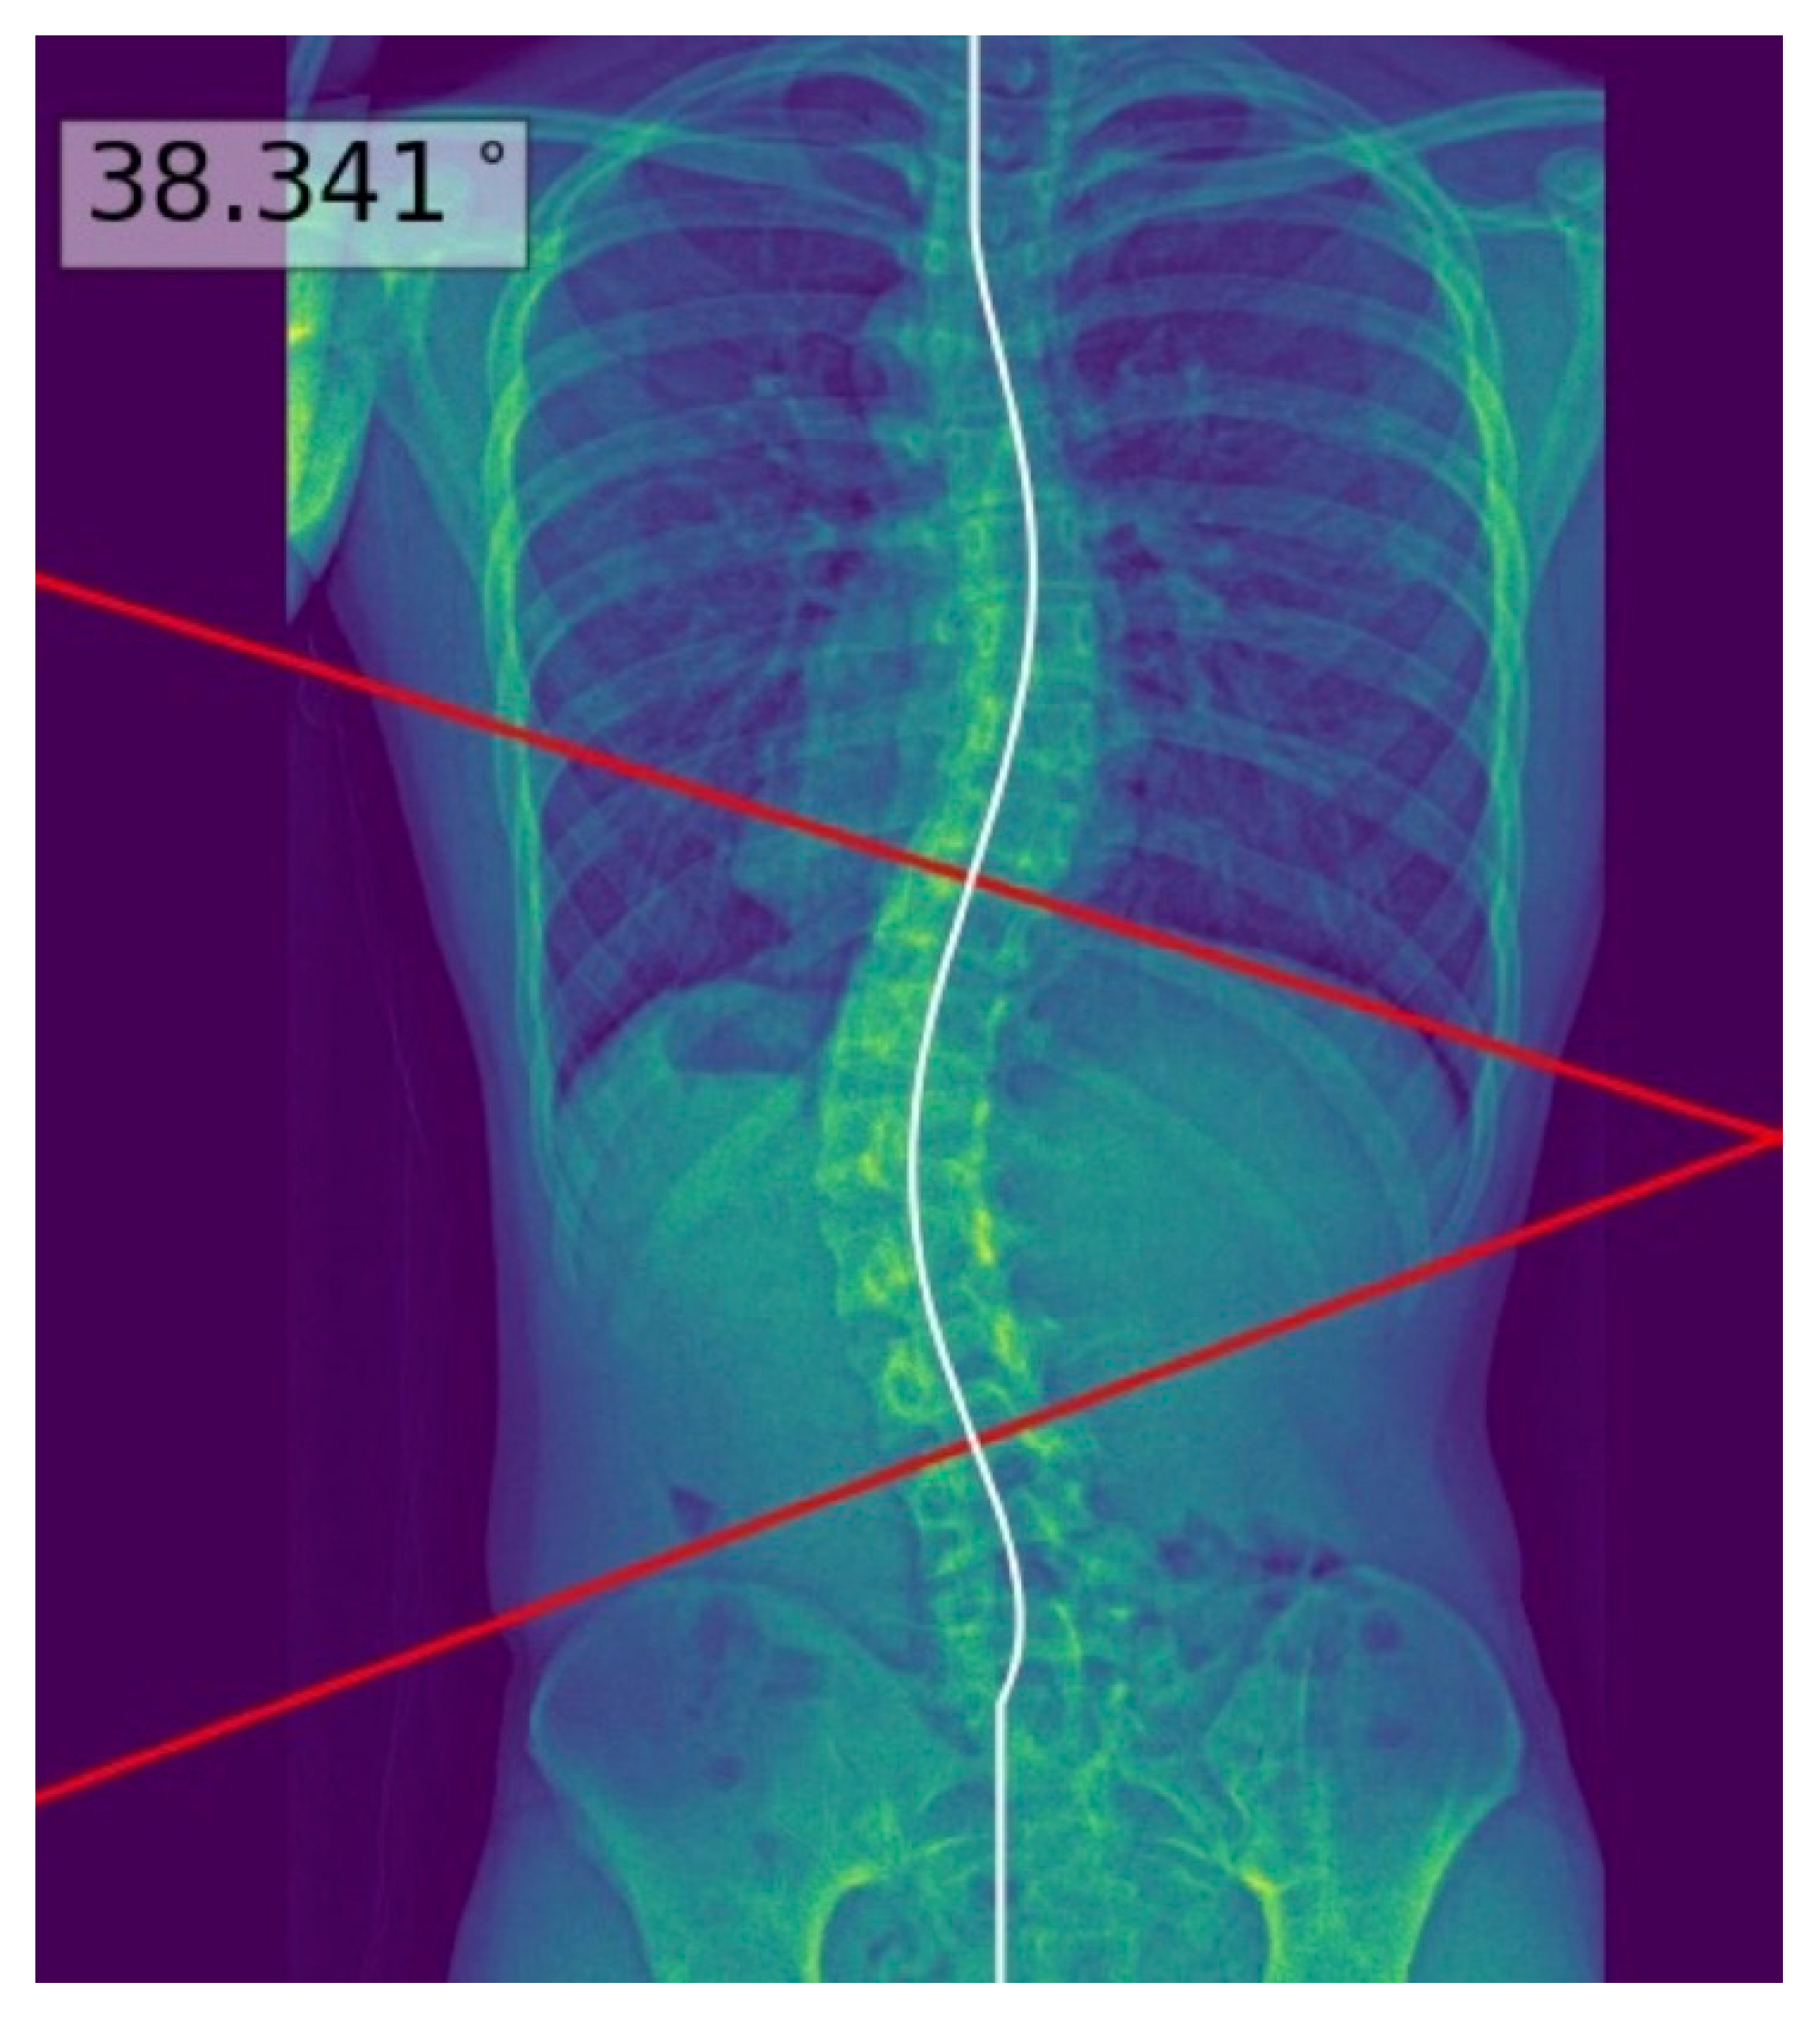

The process above allowed deep learning model masks of the whole spine (showing individual vertebrae) to be obtained and compared to the manual annotations. The model achieved a Dice similarity coefficient of 0.88 and Intersection over Union (IOU) of 84% on validation; it achieved a Dice coefficient of 0.619 and IOU of 72% on testing. Using the masks, the deep learning model determined the center of each vertebra, and extrapolated a polynomial curve along the centers. The spline technique, or the exhaustive assessment of the maximum angles between the vertebrae center line pairs to determine the largest angle, was the method of choice for the measurement of Cobb’s angle. Once the model has identified the correct points on the line, the reader could view the model prediction as extended lines and text in the top right hand corner of the image. For physicians’ review and augmentation, the model (available at the following web server: https://radweb.sha.endeavour-poc.ai/, accessed on 1 May 2022) annotated the largest possible angle in the output images, as shown in Figure 2 and Figure 3. Appendix A provides more details on the deep learning model.

The readers performed manual measurements of the major coronal curve angle without assistance from the deep learning model using the digital angle tool on the Picture Archiving and Communication System (PACS) (Centricity, GE Healthcare, Chicago, IL, USA), with the results overlaid on the images. When interpreting the radiographs with assistance from the deep learning model, the readers accessed the automated major coronal curve calculations and annotations overlaid on the images (as illustrated in Figure 2 and Figure 3). The readers could accept the model predictions or perform manual calculations using the same digital tool as per their clinical judgment, especially if the center curve alignment did not match the image.

Figure 2. Posteroanterior whole-spine radiograph for scoliosis assessment (left) with the deep learning model predictions overlaid on the processed image (right). The deep learning model extrapolated a polynomial curve along the centers of the vertebrae, and highlighted the predicted Cobb’s angle for the reader at the maximum angulated curve. This is an example of a good model prediction, with less than three degrees of difference from the reference standard.

Figure 3. Posteroanterior whole-spine radiograph for scoliosis assessment (left) with the deep learning model polynomial curve (fitted to the centers of the vertebrae) and Cobb’s angle prediction overlaid on the image (right). This is an example of a poor model prediction as it was not fitted to the inferior curve, with more than 10 degrees of difference from the reference standard Cobb’s angle.